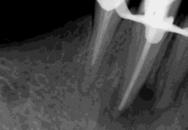

La Figura 14 muestra la imagen del carcinoma epidermoide de la mucosa yugal antes de la radioterapia. La Figura 15 muestra la radiografía dentoalveolar del incisivo central

Osteorradionecrosis de los maxilares: etiología y prevención

superior izquierdo con diagnóstico de necrosis pulpar y un área radiolúcida periapical extensa.

Las Figuras 16 y 17 muestran el tratamiento endodóntico del incisivo central superior izquierdo. Las Figuras 18 y 19 muestran el tratamiento endodóntico del incisivo central superior derecho. Se puede observar que también se realizó la endodoncia del resto radicular del incisivo central superior derecho pues no se debe realizar la exodoncia del mismo.